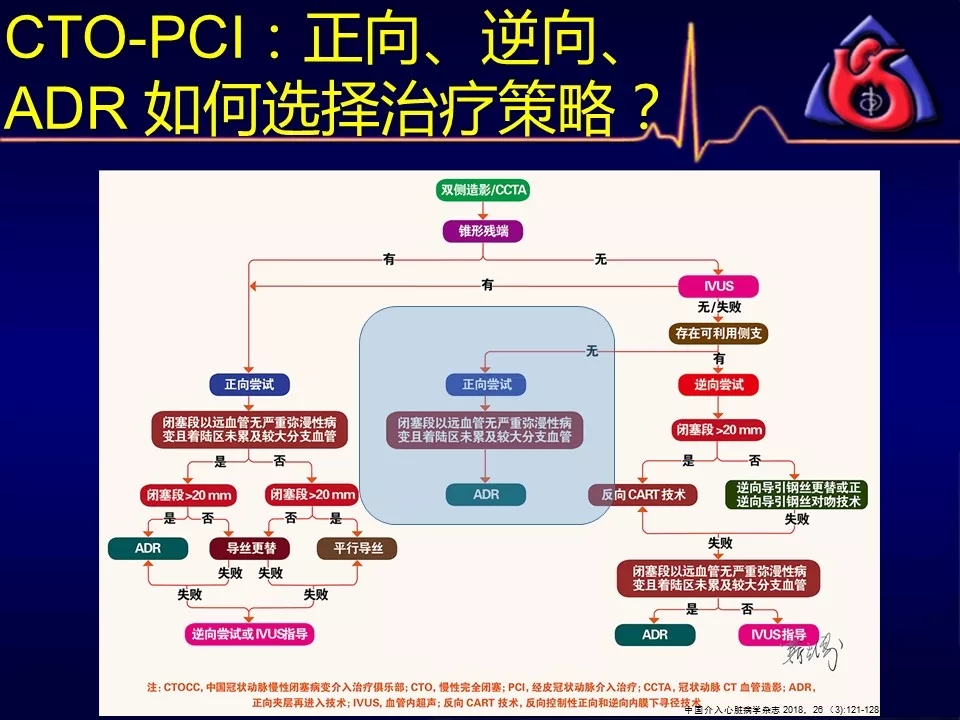

如何选择正向、逆向、IVUS指引及ADR技术?

别着急,葛雷教授带来动态幻灯版讲座:

《CTOCC CTO-PCI流程图精讲》

为您解答上述疑问